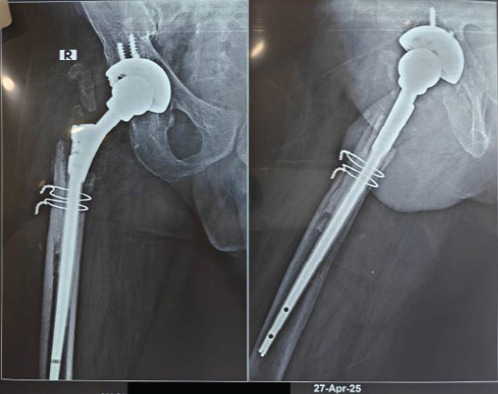

Case report: We report the case of a 52-year-old male with rheumatoid arthritis on immunosuppressive therapy, who presented with acute right hip pain, swelling, and purulent wound discharge 3 months after revision total hip arthroplasty. Initial workup revealed elevated inflammatory markers and signs of joint infection (JI). Conventional microbiological methods including Gram stain, acid-fast bacilli testing, and enrichment cultures were inconclusive. However, syndromic multiplex polymerase chain reaction (PCR) using the BioFire® JI panel detected H. influenzae within 2 h of intraoperative sample collection. The patient underwent debridement, targeted antibiotic therapy, and implant retention (DAIR). Empirical therapy with meropenem and vancomycin was promptly de-escalated to intravenous ceftriaxone, based on PCR results. Clinical recovery was marked by rapid decline in C-reactive protein, resolution of symptoms, and a successful switch to oral therapy. At 6-week and 16-week follow-up, the patient was asymptomatic, with normal inflammatory markers and radiographs, and a functioning retained implant.